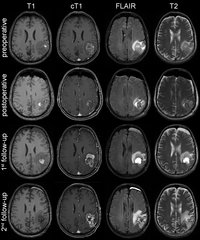

389. Künstliche Intelligenz hilft, Therapieansprechen von Hirntumoren besser zu beurteilen

Gemeinsame Pressemitteilung des Deutschen Krebsforschungszentrums (DKFZ) und des Universitätsklinikums Heidelberg (UKHD)